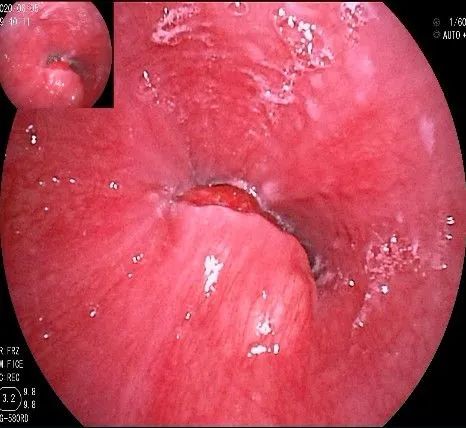

倒镜观察,可见贲门部一个明显的隆起,中央部分的凹陷,是4天前取活检留下的。

正镜观察,瘤体就在贲门部齿状线的下方。